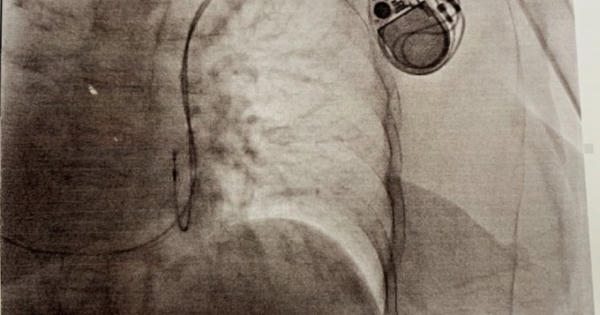

TP.HCM: Cứu nữ bệnh nhân có trái tim bên phải, nhịp tim "siêu chậm".

Bệnh nhân nhập viện khi đột ngột choáng rồi ngất, tím tái và ngừng thở nguy kịch.